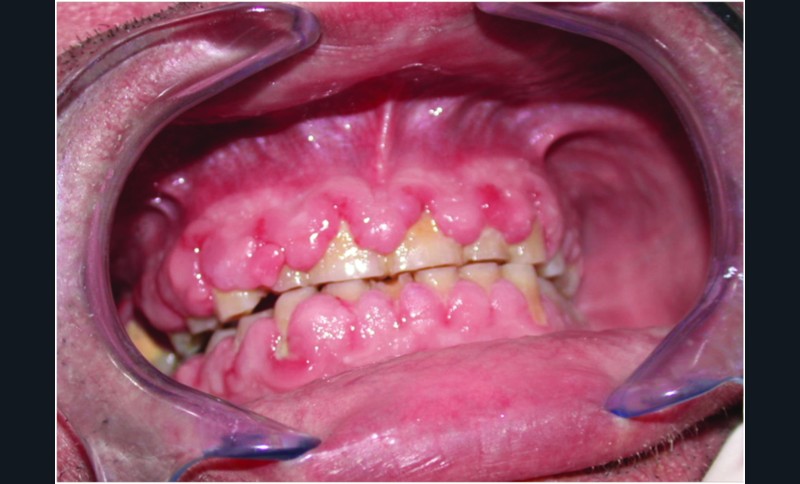

Examen clinique. La gencive était hypertrophique. Elle formait des nodules fibreux, sessiles, ayant tendance à confluer, et plutôt pédiculés dans la région des papilles. La gencive marginale était associée à de la plaque dentaire.

Histoire de la maladie. Depuis trois ans, le patient présentait une hypertrophie gingivale qui recouvrait en partie la face vestibulaire des dents.